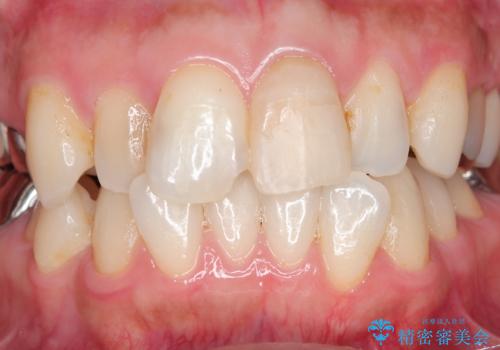

- 自転車で転倒してしまい、前歯を折ってしまい、痛みと見た目の改善を希望され来院されました。

もともと根管治療の為されて歯が折れてしまっているので、根管治療を行い審美的なセラミック治療を行う治療計画としました。

周囲の歯と調和した審美的な仕上がりに満足いただくことができました。